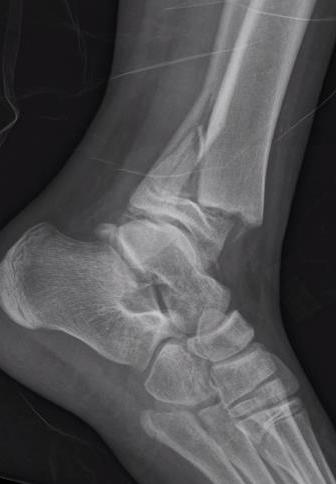

Triplanar Fracture

Definition

Fracture in coronal, sagittal and transverse planes

- crosses epiphysis

- passes through growth plate

- extends into metaphysis

Xray

AP xray: Salter-Harris type III / Tillaux

Lateral xray: Salter-Harris Type II

CT

Coronal images: Salter-Harris type III

Sagittal images: Salter-Harris type II

Axial images: 3 point star